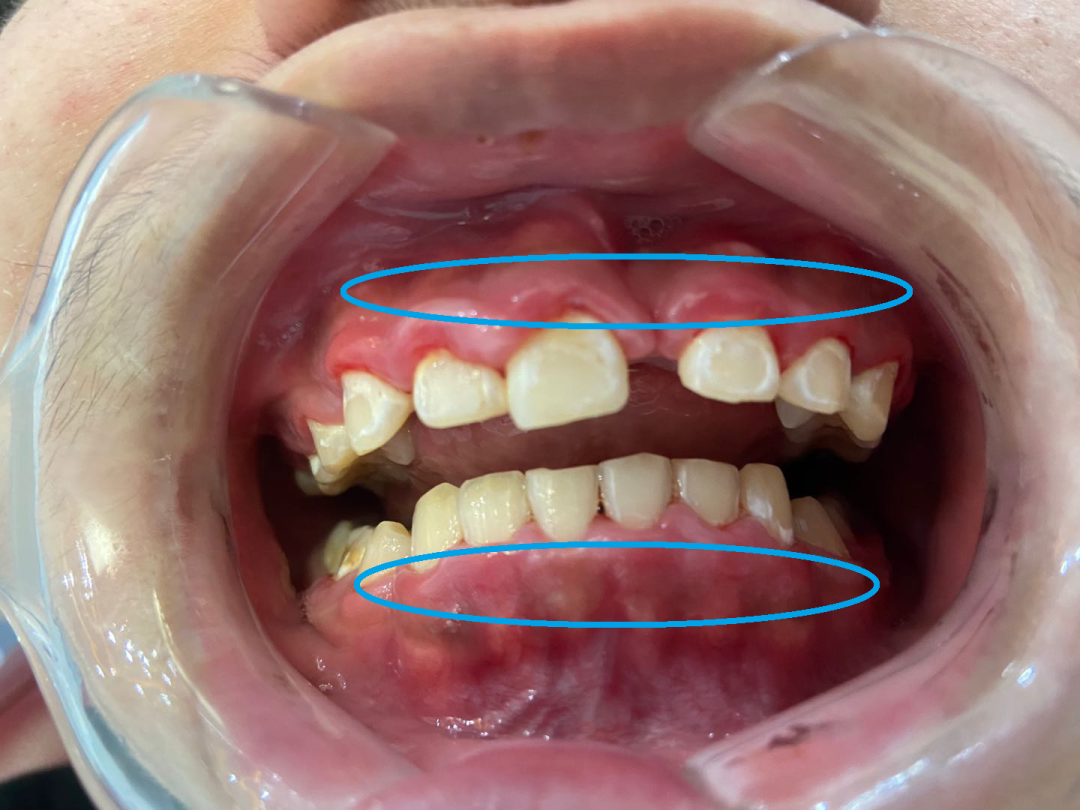

一位患者咨询牙齿矫正时

想要进行二次正畸治疗

但牙医发现他全口牙龈红肿、肥厚明显

影响到了正畸治疗,建议他先进行牙周处理

经医生初步诊断为慢性龈炎

需要进行龈上洁治(洗牙)与龈下刮治

- 初诊时,患者的口腔状况 -